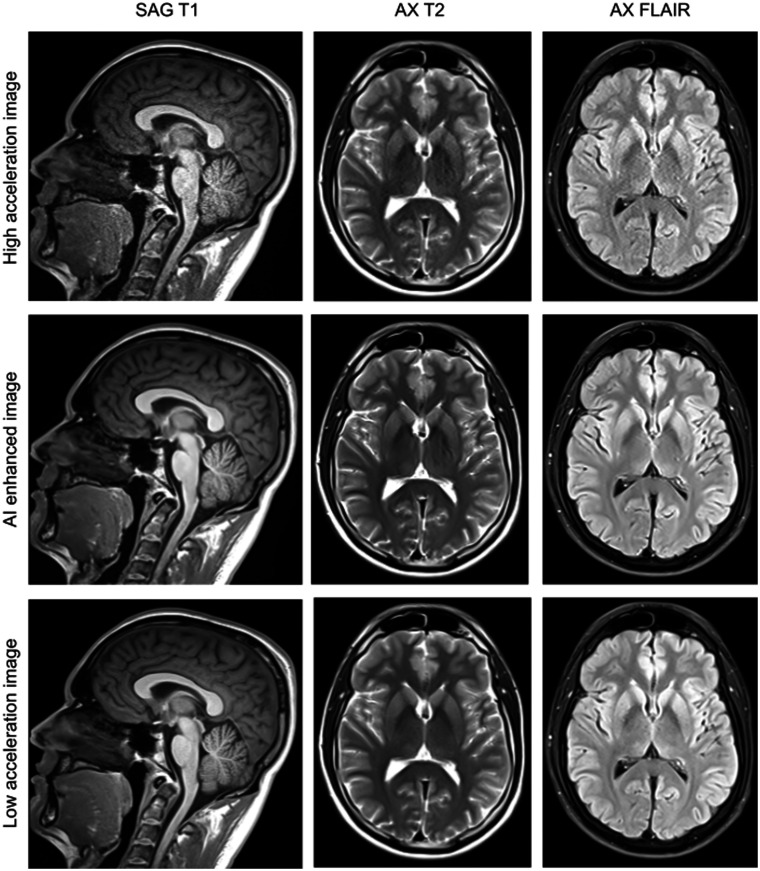

Purpose: To evaluate a vendor-agnostic AI-based approach to remove image degradation artifacts in highly accelerated MRI scans, improving image quality and reducing scan time.

Results: Images from 101 adults from 5 sites and 6 scanner models from different vendors were enrolled. 89% of imaged subjects had noteworthy imaging features or pathology. Model outputs were rated superior to model inputs (P < .001) and most were either non-inferior (P inf  > .05) or superior (P sup  < .05) to baseline images in qualitative metrics of image quality and feature visibility. Quantitative evaluation of signal-to-noise ratio and contrast-to-noise ratio improved for model outputs compared to inputs (P < .001) or baseline images (P < .005). Apparent resolution measured using the full width at half maximum or minimum was either enhanced (P sup  < .05) or preserved (non-superior P sup  > .05 and non-inferior P inf  > .05). The scan time was reduced by an average of 29% (19%-41% per sequence).

Conclusion: This vendor-agnostic AI-based method achieved robust scan time savings without loss of image quality, potentially allowing for reduced cost and improved patient experience.